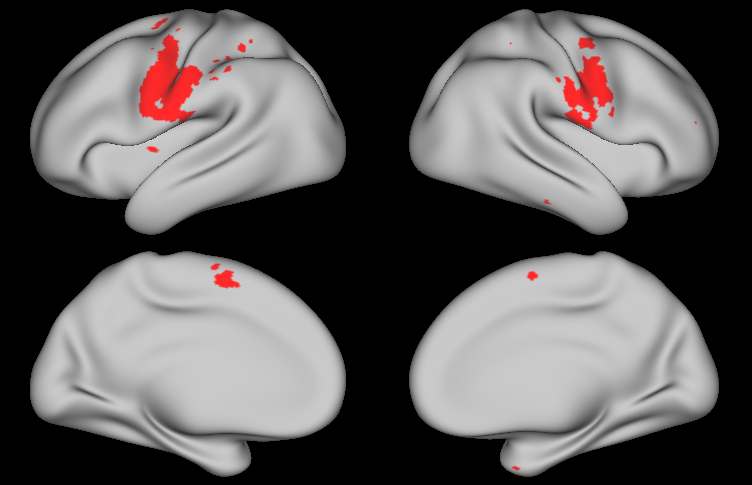

Figure LABEL:fig:app:beta_subj displays the Bayesian estimates of activation amplitude (posterior means) for the visual cue and tongue tasks, along with the classical GLM estimates, for one randomly selected subject. The remaining tasks are shown in Appendix C. Both sets of estimates are noisy, due to the high levels of noise in fMRI data and relatively short duration of the tasks performed for each individual subject (303030 seconds for the visual cue; 242424 seconds for the tongue task); however, the Bayesian estimates are substantially smoother than the classical estimates, even though the data was smoothed prior to fitting the classical GLM but not the Bayesian GLM. Figure LABEL:fig:app:beta displays group-level estimates of activation amplitude based on the classical and Bayesian GLM approaches. For the Bayesian GLM, the results using the joint modeling approach and the two-level modeling approach with the sampling method described in Section 3.1 are both displayed. In both the subject-level and group-level estimates, the activation fields for each task are generally as expected: during the visual cue, the visual and orbitofrontal (decision making) regions are highly active, while the somatomotor (motor planning) region is activated to a lesser degree; during the tongue movement task, the area of the motor cortex associated with the tongue shows a strong degree of activation; and the remaining motor tasks activate the expected areas of the motor cortex (see Figures S4 and S5 in Appendix C). Compared with the classical GLM, the Bayesian GLM results in smoother estimates of activation, as it accounts for dependence in the degree of activation between neighboring locations. As hypothesized, the two-level modeling approach tends to result in somewhat oversmoothed estimates, compared with the joint modeling approach.

Figure LABEL:fig:app99 shows the regions of activation identified by thresholding the joint PPM excursion function for each task, along with those identified through the classical GLM with FDR and FWER correction, using significance level 0.010.010.01 in each method. For the Bayesian GLM, regions of activation at activation threshold γ=0𝛾0\gamma=0 are shown in purple, while those at γ=0.027𝛾0.027\gamma=0.027, corresponding to 1%percent11\% of the global baseline signal, are shown in red. Several effects are clearly notable. First, the areas of activation based on controlling the FWER in the classical GLM are very conservative. This is a well-known issue with this approach that worsens as the number of locations increases, which is likely why FWER correction produces reasonable results in the simulation study but very conservative results on real fMRI data. FDR control results in significantly larger areas of activation, reflecting an increase in power while maintaining a known degree of false positive control. Second, the areas of activation based on γ=0𝛾0\gamma=0 in the Bayesian GLM are similar to those based on FDR control in the classical GLM, but are smoother and somewhat larger. This likely reflects an increase in power resulting from incorporating spatial dependencies in the Bayesian GLM, as observed in our simulation study. Third, compared with the joint model, the areas of activation based on the Bayesian two-level model are smoother but similar in size. This illustrates that while the two-level approach tends to result in somewhat oversmoothed estimates, the sampling method described in Section 3.1 is able to appropriately account for uncertainty in the subject-level estimates when fitting the group-level model. Finally, the increased power in the joint PPM results in widespread areas of activation based on γ=0𝛾0\gamma=0, while the more biologically meaningful threshold of γ=0.027𝛾0.027\gamma=0.027 (1%percent11\% of the baseline signal) results in more conservative areas of activation that correspond well to the highly activated areas shown in yellow in Figure LABEL:fig:app:beta.